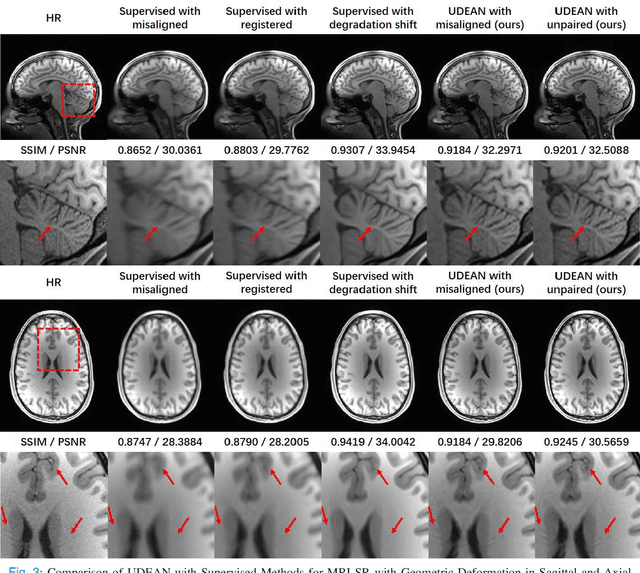

Abstract:High-resolution (HR) MRI is critical in assisting the doctor's diagnosis and image-guided treatment, but is hard to obtain in a clinical setting due to long acquisition time. Therefore, the research community investigated deep learning-based super-resolution (SR) technology to reconstruct HR MRI images with shortened acquisition time. However, training such neural networks usually requires paired HR and low-resolution (LR) in-vivo images, which are difficult to acquire due to patient movement during and between the image acquisition. Rigid movements of hard tissues can be corrected with image-registration, whereas the alignment of deformed soft tissues is challenging, making it impractical to train the neural network with such authentic HR and LR image pairs. Therefore, most of the previous studies proposed SR reconstruction by employing authentic HR images and synthetic LR images downsampled from the HR images, yet the difference in degradation representations between synthetic and authentic LR images suppresses the performance of SR reconstruction from authentic LR images. To mitigate the aforementioned problems, we propose a novel Unsupervised DEgradation Adaptation Network (UDEAN). Our model consists of two components: the degradation learning network and the SR reconstruction network. The degradation learning network downsamples the HR images by addressing the degradation representation of the misaligned or unpaired LR images, and the SR reconstruction network learns the mapping from the downsampled HR images to their original HR images. As a result, the SR reconstruction network can generate SR images from the LR images and achieve comparable quality to the HR images. Experimental results show that our method outperforms the state-of-the-art models and can potentially be applied in real-world clinical settings.